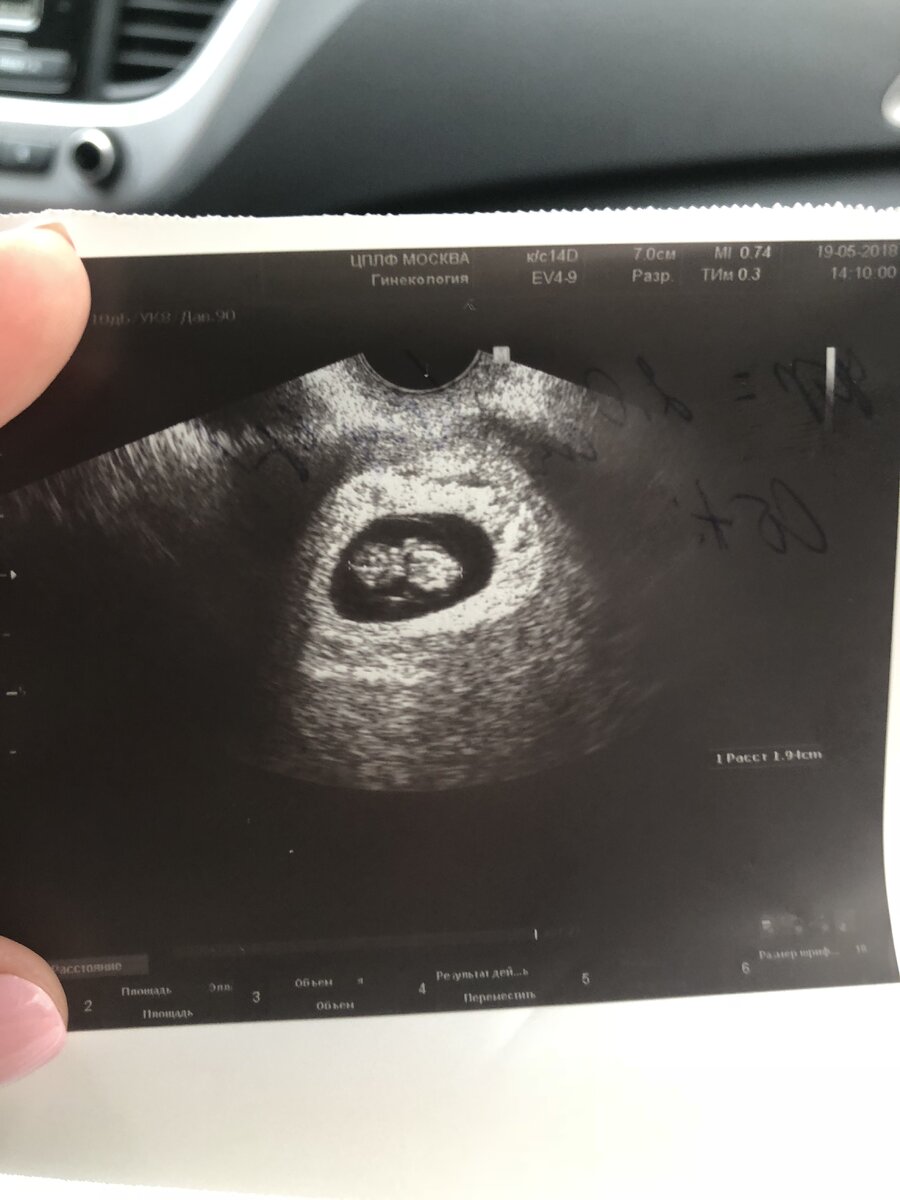

В итоге на УЗИ только на 5 недели могли что то увидите, о боже, как я радовалась...но на фото особо не поймёшь, что там нарисовано, но я понимала, что это наш любимый малыш...в клинику ездила на Баррикадной Медси, моя самая любимая Клиника, она большая,новая, отличные специалисты,очередей нет.

7 недель